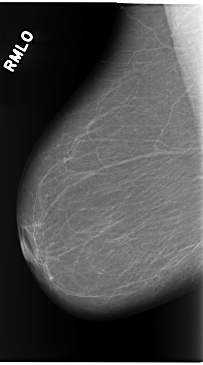

C_0119_1.RIGHT_MLO

RIGHT_MLO LINES 5840 PIXELS_PER_LINE 3248 BITS_PER_PIXEL 12 RESOLUTION 50 NON_OVERLAY